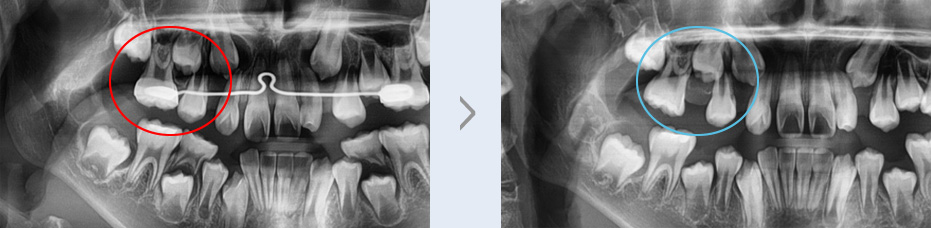

유치 조기 상실의 경우 적절한 치료 시기를 놓친다면 영구치가 매복되거나 심한 덧니로 이어질 수 있는 만큼

세심한 관찰과 빠른 치료가 필요합니다.

가철식 장치를 통해 확보한 공간으로 작은 어금니가 정상적인 위치에 나올 수 있게 되었습니다. 영구치가 매복

되거나 심한 덧니가 발생하는 것을 예방할 수 있는 조기 치료로 고른 치열을 가질 수 있게 되었습니다.